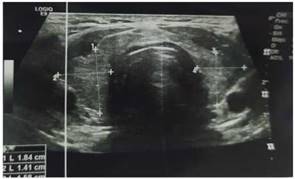

Cuatro meses después del cuadro inicial, el paciente fue hospitalizado nuevamente por cuadro de 4 horas de evolución caracterizado por presentar parálisis flácida de miembros superiores e inferiores, acompañado por parestesias en miembros inferiores, mialgias y disnea, sin alteración de funciones superiores, al examen físico con presión arterial 110/70, frecuencia cardíaca 90 latidos por minuto, tiroides de tamaño normal, sin alteraciones cardiopulmonares, sin temblor distal en manos. Entre los estudios de laboratorios realizados en emergencias destacó la presencia de hipopotasemia severa de 2,0 mEq/l. Con la sospecha de PPHT, se solicitó estudios de función tiroidea con resultados de TSH 0,01 uUI/ml (rango de referencia 0,4 y 4,5), T4 libre 3,09 ng/ dl (rango de referencia 0,8 y 1,65), anticuerpos anti TPO 552 UI/ml (rango de referencia 0 a 95) y anti tiroglobulina 211 UI/ml (rango de referencia 0 a 30), tiroglobulina 17 ng/ml (rango de referencia 0 a 55), ecografía tiroidea que reportó de tamaño y morfología normal, sin evidencia de lesiones nodulares (Figura 1), electrocardiograma sin alteraciones (Figura 2). Se inició tratamiento con fármacos antitiroideos y betabloqueadores, además de jarabe de potasio, el mismo que se disminuyó de forma gradual hasta su suspensión. Hasta la fecha el paciente mantiene tratamiento con tiamazol 20 mg por día, con control adecuado de la función tiroidea, sin nuevos episodios de debilidad y/o hipopotasemia. Se presenta la evolución de la concentración de potasio sérico en el Figura 3.

Figura 1. Ecográfica tiroidea: reportada de tamaño y morfología normal, lóbulo tiroideo derecho de 52x18x14x, lóbulo tiroideo de 50x15x14 mm. Parénquima tiroideo homogéneo, sin evidencia de lesiones sólidas ni quísticas. Al Doppler color sin alteraciones.